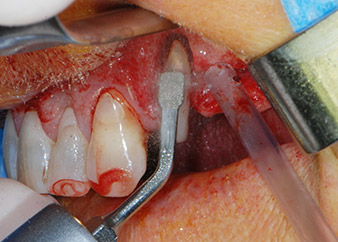

Si è mantenuta , tuttavia, l'idea iniziale di conservare entrambi i denti come appoggi temporanei del ponte durante il periodo di sei mesi per l'osteointegrazione degli impianti. In seguito la situazione si sarebbe assestata. In primo luogo, in un tentativo di risolvere il problema entro-periodontale, la superficie radicolare rimanente è stata attentamente sbrigliata con apparecchiatura piezoelettrica (Piezomed di W&H con l'attacco S1 a spatola, progettato in origine per l'erosione della parete laterale del seno mascellare) Fig. 4).

Parodonto

Fig. 4: Per conservare il dente come appoggio temporaneo, il periodonto è stato sbrigliato con apparecchiatura piezoelettrica...

apice buccale del dente 24

Fig 5: ...e l'apice buccale del dente 24 è stato abraso con lo stesso strumento (apicectomia).